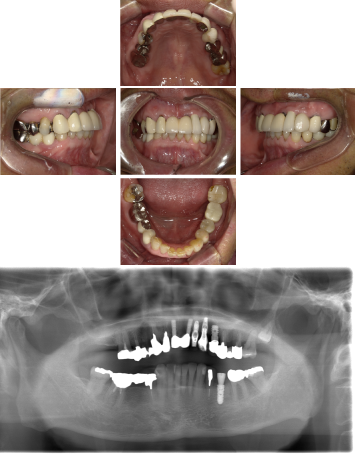

70代 女性 インプラント治療(GBR)

| 年代・性別 | 70代・女性 |

|---|---|

| 主訴 | 抜歯適応になってしまった所にインプラント治療希望。 |

| 部位 | 右上3・5(右上345のブリッジ)、右下6・7 左上4・6(左上456のブリッジ)、左下6・7 |

| 治療期間 | 約14ヶ月 |

| 費用 | ¥3,740,000(税込) |

| 副作用・リスク |

|